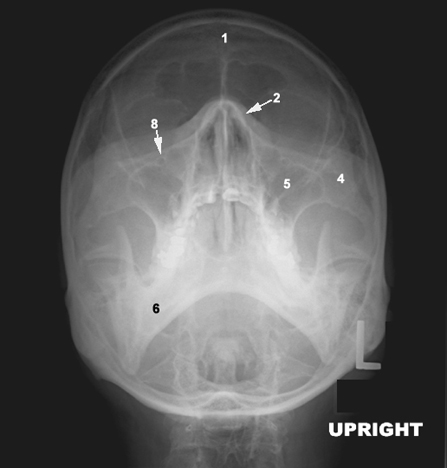

1: Frontal bone  2: Nasal bone  4: Zygomatic  5: Maxilla

6: Mandible  8: Infra orbital foramen